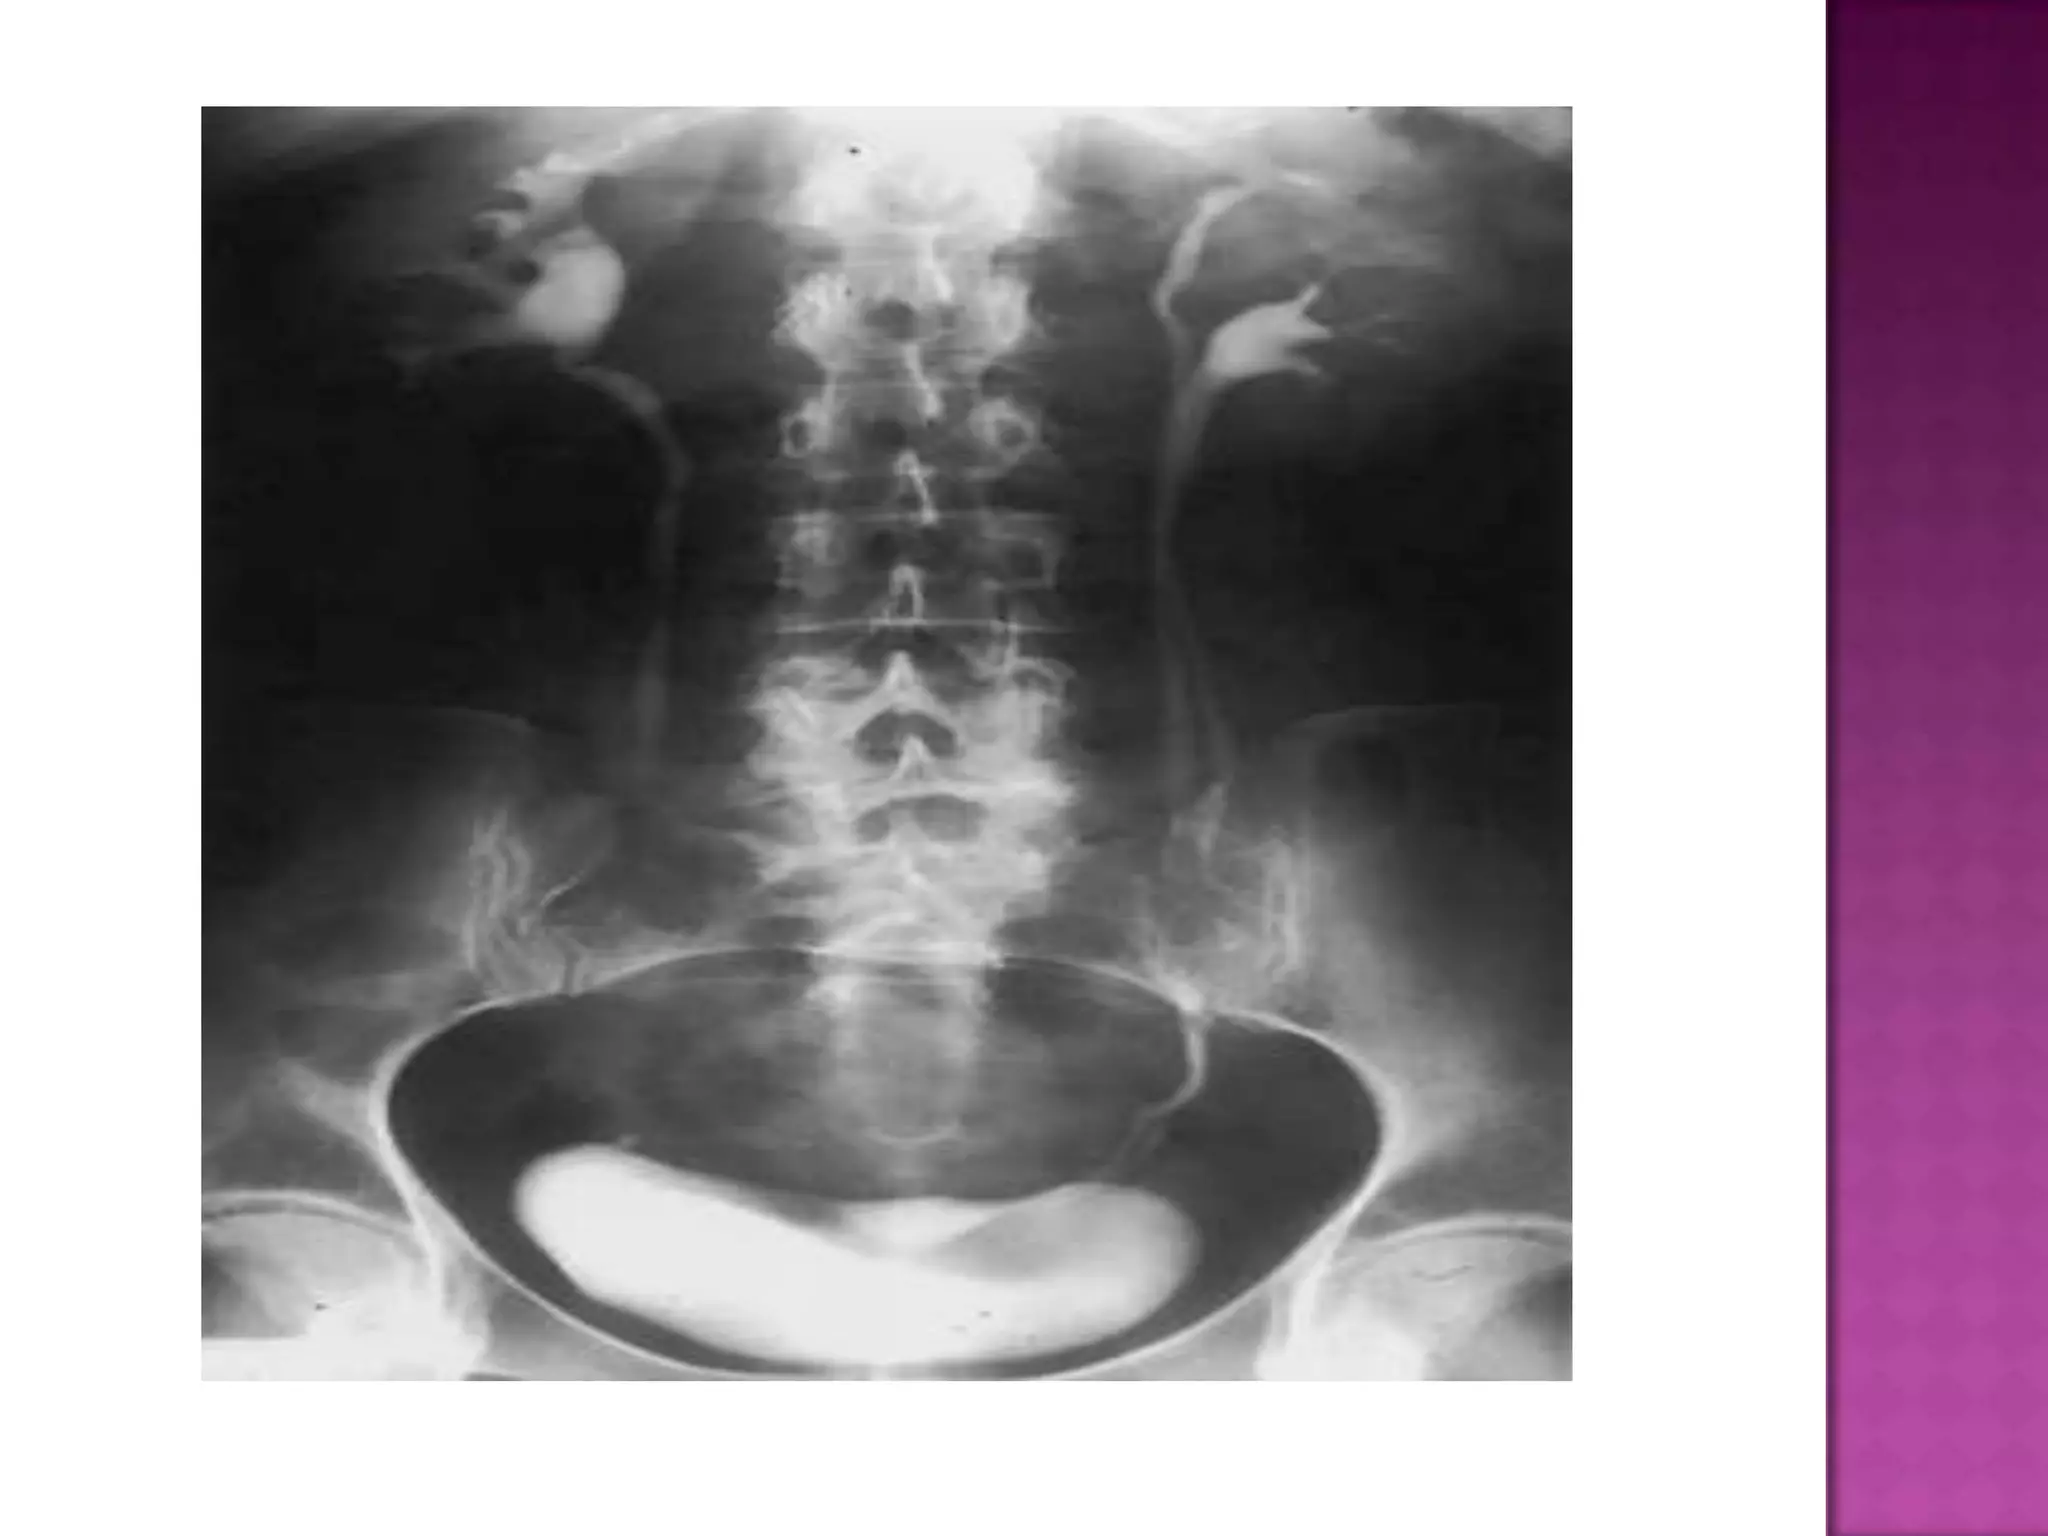

The plain KUB

shows lumbar

spondylosis

with marked

scoliosis and

obvious

asymmetrical

thickness of

the lateral

abdominal wall

musculatures.

The plain KUB showslumbar spondylosis with marked scoliosis and obvious asymmetrical thickness of the lateral abdominal wall musculatures.